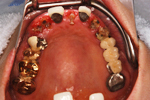

症例 4

術前

術後

術中

骨を作っている途中